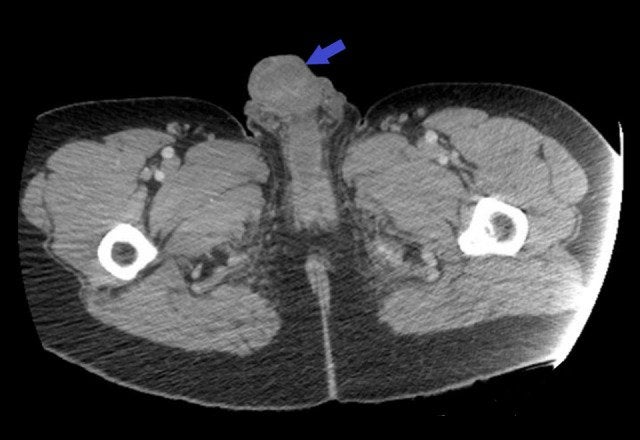

Tras examinarlo, los doctores vieron que el pene estaba hinchado, negro, ulcerado y exudaba una secreción maloliente. Además, el paciente contaba con un largo historial de uso de drogas por vía intravenosa. Según explicaron en el trabajo:

La cocaína es una de las “drogas disponibles más peligrosas. Esto se debe a que es altamente adictiva, ya que se puede inhalar, fumar o disolver e inyectar en una vena. Cuando se inyecta, puede desencadenar la inflamación de los vasos sanguíneos, lo que puede causar gangrena, la muerte del tejido corporal.

La vena dorsal es un lugar inusual para inyectarse, pero no es raro que los usuarios de drogas usen nuevos sitios de inyección una vez que otros, como las venas del brazo, se dañan. El paciente rechazó cualquier cirugía para cortar el tejido moribundo. Fue tratado con un cóctel de fuertes antibióticos intravenosos durante cinco días y luego otros cinco días con antibióticos orales, junto con el cuidado de la herida.